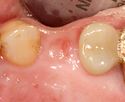

زراعة الأسنان أو غرس الأسنان dental implant، هي تدخل جراحي يتعامل مع عظام الفك أو الجمجمة لدعم تعويضات الأسنان مثل التاج، الجسر، طقم الأسنان، التعويضات الوجهيية أو التي تعمل كأداة تقويم. أساس زراعة الأسنان الحديثة هو عملية حيوية تسمى osseointegration حيث المواد مثل التيتانيوم، تشكل رابطة قوية بالأسنان.

في طب الأسنان، زراعة الأسنان هي كل مايتعلق بزرع المواد الصلبة تحت الغشاء المخاطي السنخي، أو تحت السمحاق، أو في العظم، وذلك للمساعدة على تثبيت الصفائح السنية التعويضية في الفم. والفرق الرئيس بين هذه الزروع والزروع في باقي أنحاء الجسم، كزرع صمام القلب، وعنق المفصل، أن التعامل في الزروع الأخيرة يكون مع مادة غرست في جوف مغلق، أما في الغرسة الفكية فإن بروز المهاميز عبر الغشاء المخاطي إلى جوف الفم يؤدي إلى «غرسة مفتوحة» مما يترك صلة واضحة بين جوف الفم وما فيه من جراثيم والجوف الحاوي للغرسة.

إن أمام عملية غرس البدائل للأسنان طريقاً وعرة، إذ إنه مع تطور المواد المغروسة وحسن تقبلها من الأنسجة العظمية المحيطة، تبقى مشكلة بروز المهماز من الغرسة من خلال الغشاء المخاطي إلى جوف الفم قائمة، مما يجعل للغرسة وضعاً خاصاً تكون فيه على صلة بجوف الفم وبما يحمله من مجموعات جرثومية مؤذية لا يمكن منعها من اجتياز المنطقة المحيطة بعنق الغرسة إلى العظم. وتدل الإحصاءات العالمية الحديثة لنتائج الغرسات المطوَّرة من مادة التيتان، على وصول نسبة النجاح إلى 85% في خمس سنوات فما فوق من تطبيق الغرسة.